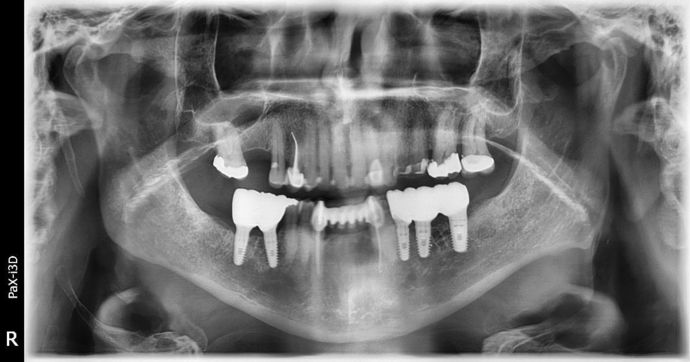

Dental Implants: Case 2 - Sweeny

Another Great case we finished up! Patient had lost a bridge on lower left side due to a cracked root and large decay on the other anchor tooth. Bridge was sectioned and teeth were removed. On the right side, wisdom tooth was hyper-erupted and had poor prognosis due to bone loss. Wisdom tooth was removed. Left side had bone graft placed and three months later 3 implants were placed. Right side had 2 implants placed at the same time. After healing, Implants were restored with bridge on left side and separate crowns on right side. The model is of the patient before surgery (no photos were available), actual photo is of patient after restorations finished. LOVE THE OUTCOME!